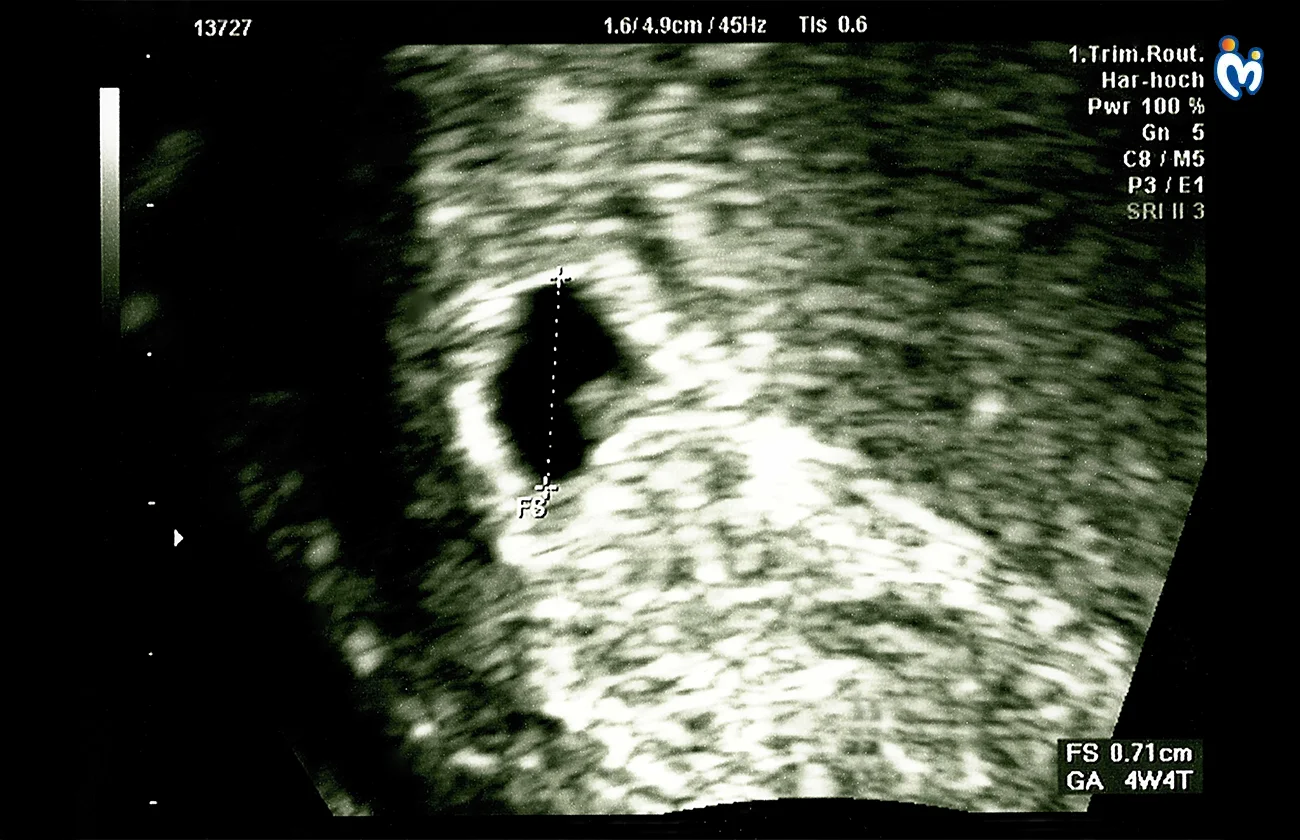

Your baby now has two layers of cells, which will later develop into organs. Baby How Much Has Baby Developed 1732515826426